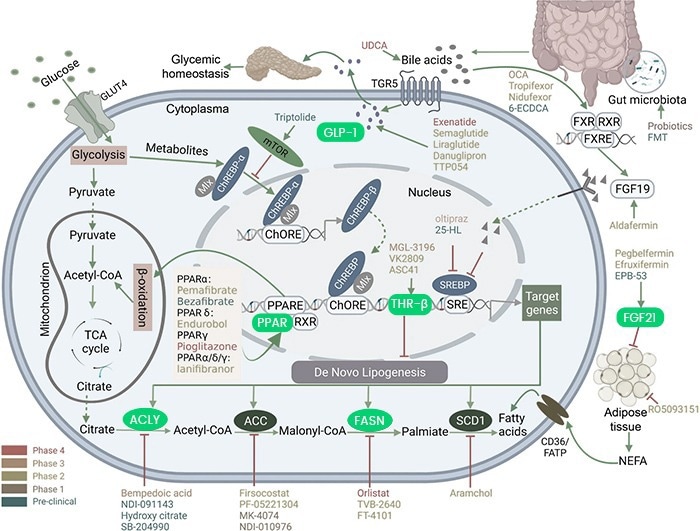

For example, when FASN activity is out of balance, it can lead to hepatic steatosis, a key feature of NASH, despite its essential role in liver fat processing. In NASH, disrupted THR-β signaling messes up the metabolic balance, causing more fat buildup and inflammation.

When NR1H4/FXR, a nuclear receptor, does not function appropriately in NASH, it can result in bile acid-related liver damage and inflammation. GLP-1R issues in NASH can lead to insulin resistance and more fat in the liver.

Altered PPARA signaling in NASH contributes to messed-up fat processing and liver inflammation. Importantly, FGF19 and FGF21 are essential targets for drugs that regulate bile acids and energy in the liver during NASH. ACLY might also contribute to excess liver fat by making new fats. Understanding these roles is critical to developing effective ways to treat NASH.

Inhibiting FASN aims to reduce fat buildup in the liver and reduce inflammation. Preclinical studies show the effectiveness of NR1H4/FXR agonists like Tropifexor and Nidufexor in addressing liver damage and inflammation related to bile acids. GLP-1R agonists like Semaglutide and Liraglutide can potentially improve insulin sensitivity and reduce liver fat.

FGF19 analog (Aldafermin) and FGF21 receptor agonist (Pegbelfermin) also promise to reduce liver fat and improve liver function. In preclinical studies, the THR-β agonist Resmetirom helps regulate metabolic balance and improves liver fat buildup.

PPARA agonists can potentially improve lipid metabolism and reduce inflammation in NASH. Ongoing investigations into ACLY inhibitors like Bempedoic acid hold promise for their therapeutic benefits.

Targeting Glucose and Lipid Metabolism in NASH: Overview of Drug Actions. Image Credit: Xu, X., Poulsen, K.L., Wu, L. et al.